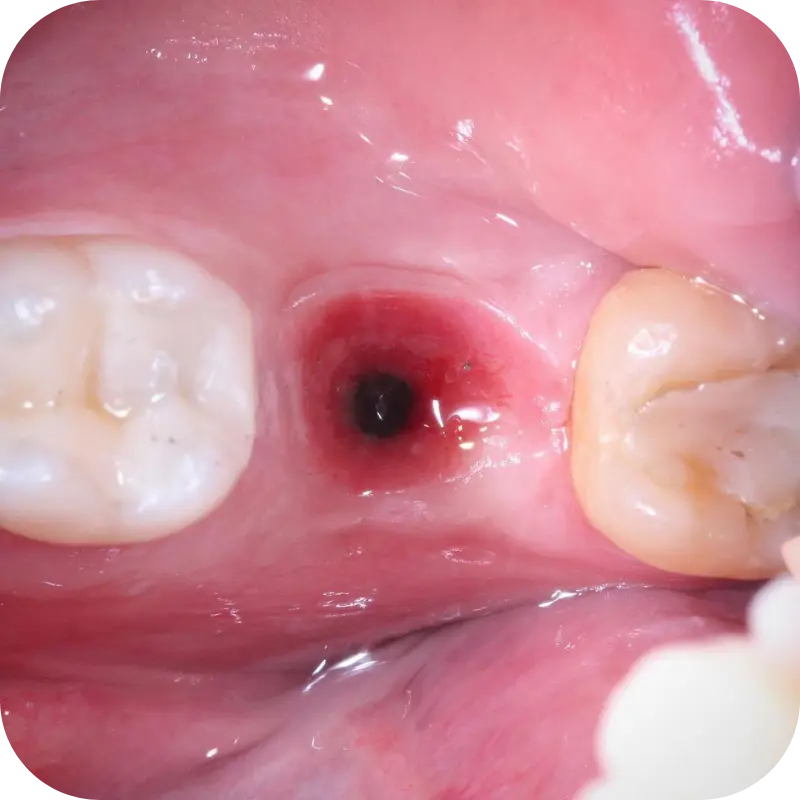

• Condicionamento gengival

• Condicionamento de provisório